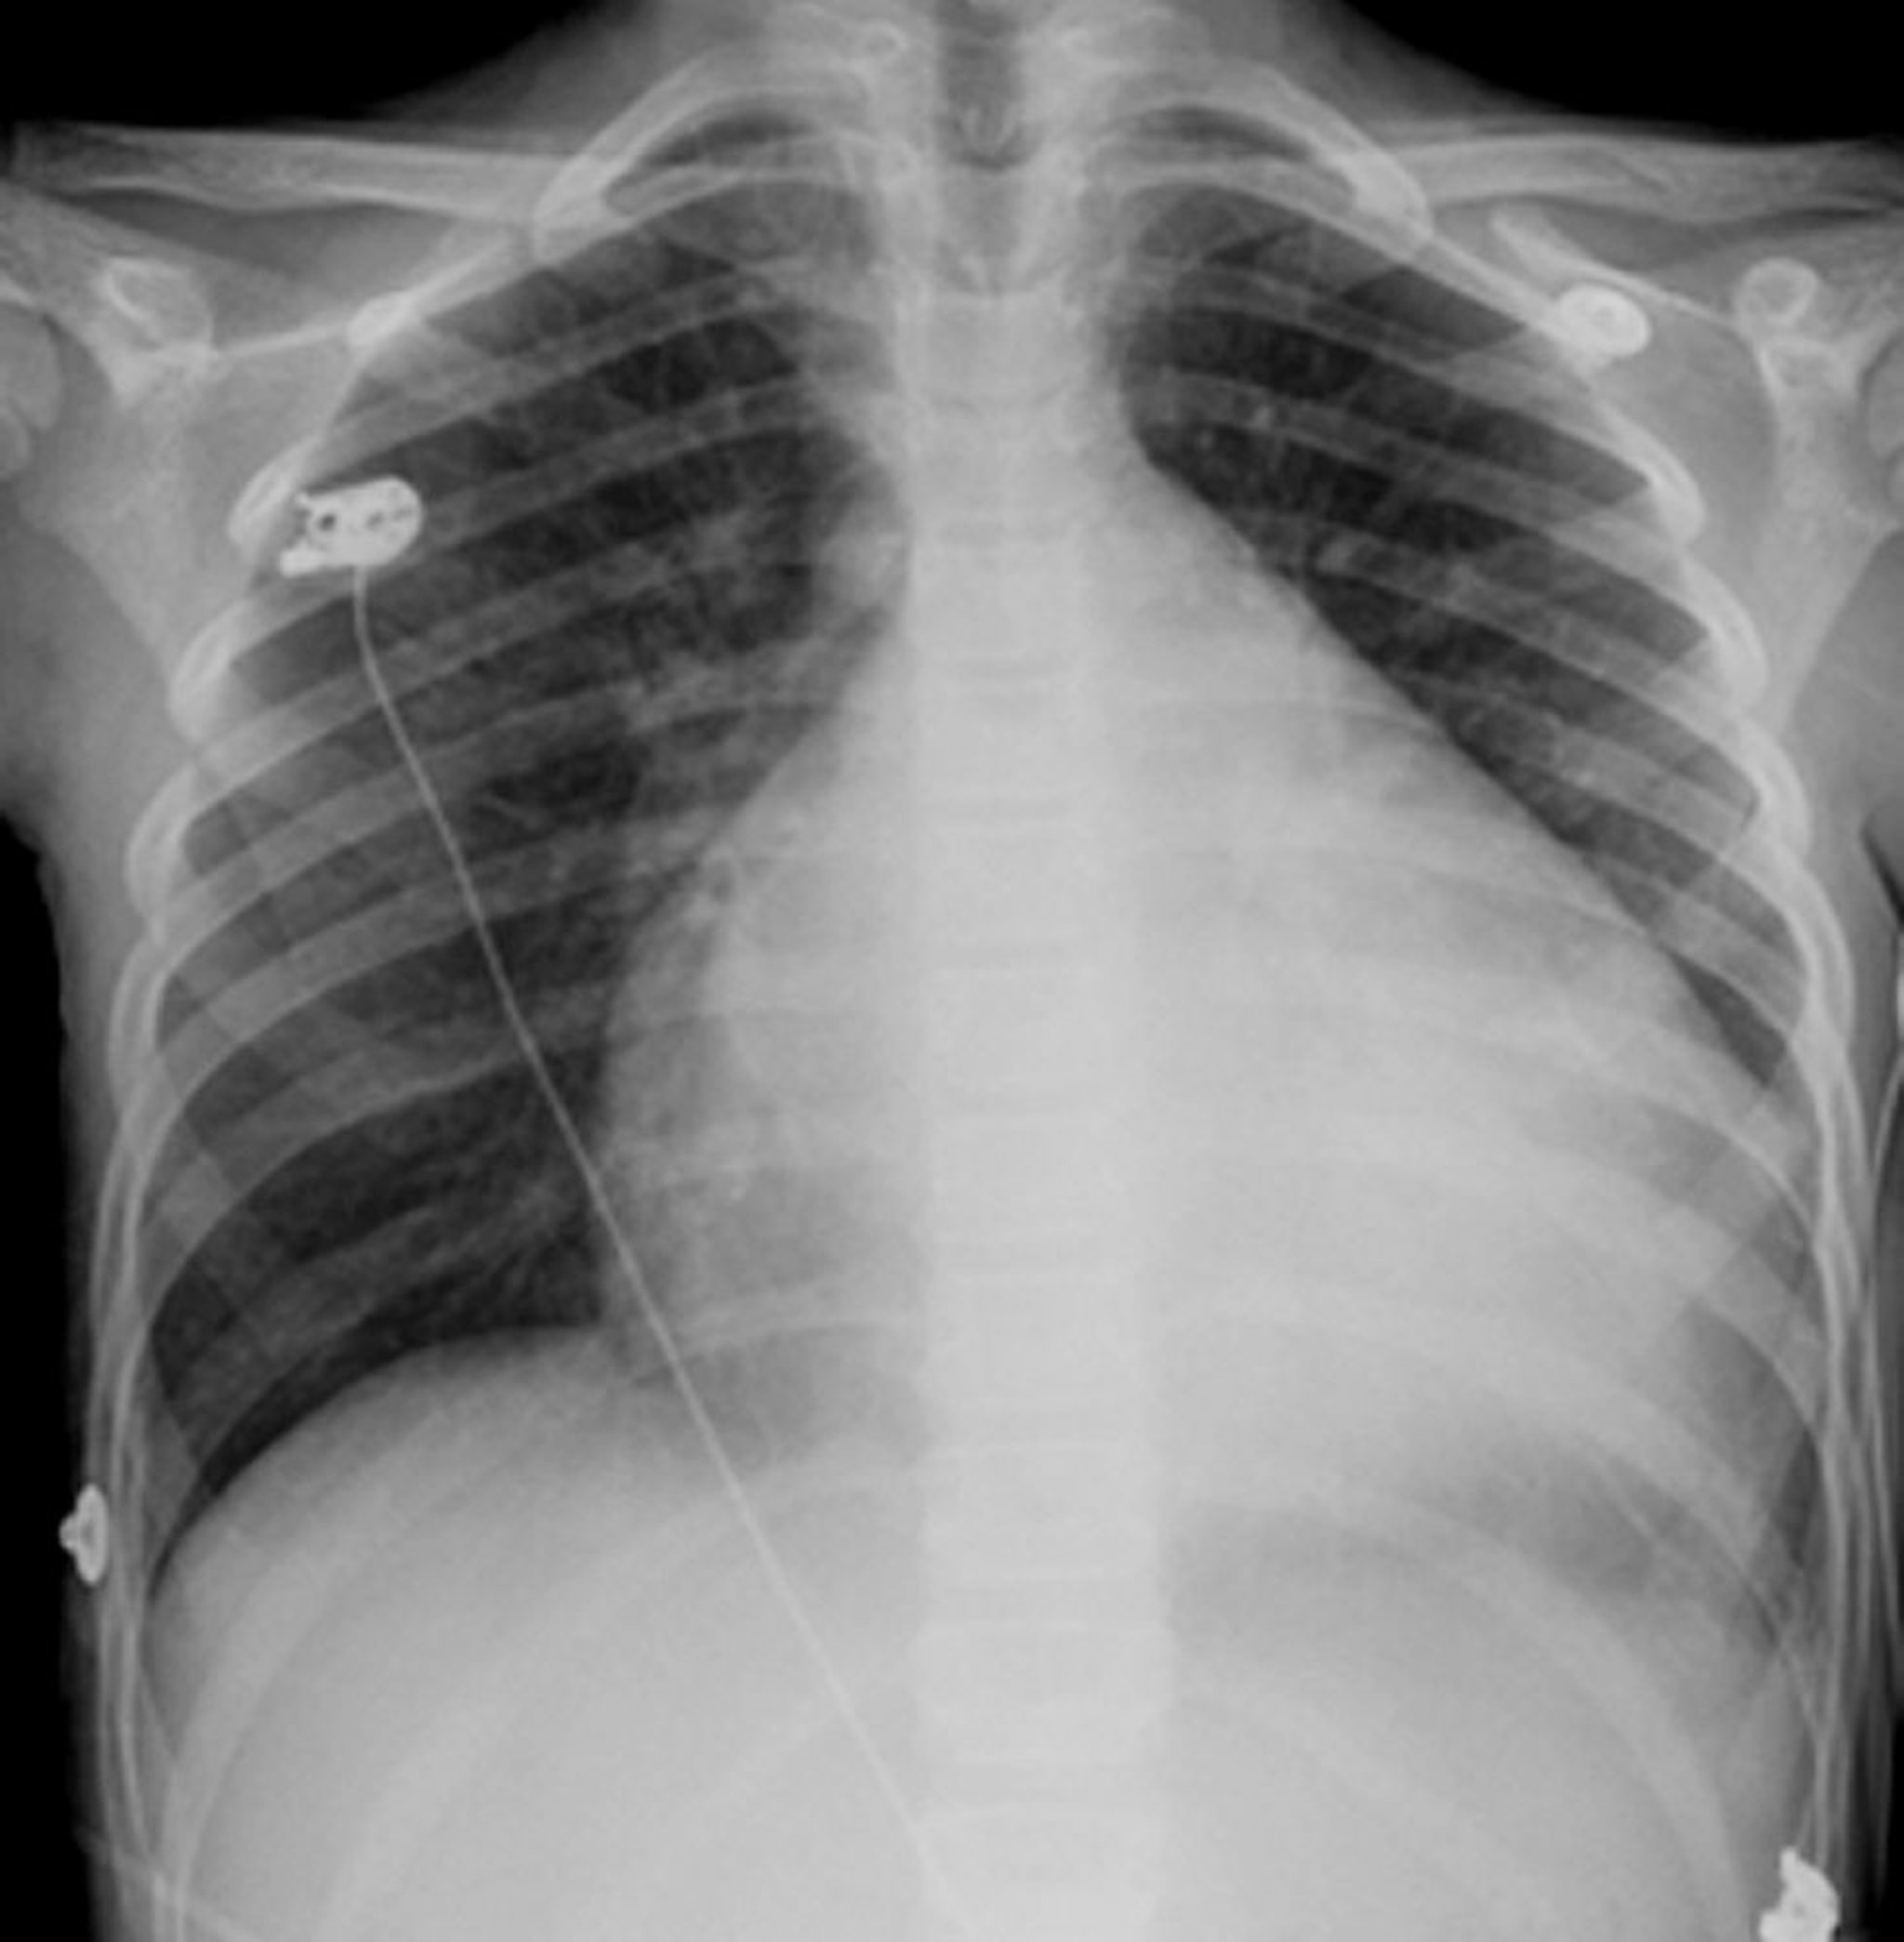

Hipertrofia cardíaca

El corazón es la estructura globular de color blanco situada en el centro del tórax. Por lo general, ocupa menos de la mitad del tórax, pero en esta persona que tiene un corazón agrandado (miocardiopatía), el corazón ocupa casi 3/4 del tamaño del tórax.